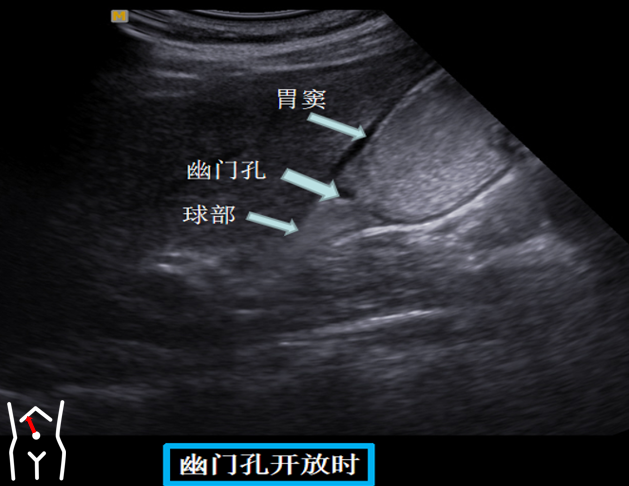

患者从右卧位改成平卧此时头也随着患者改变体位而由横切改为纵切在脐孔与右肋缘连线处扫出胃窦幽门管幽门孔球部降部水平部